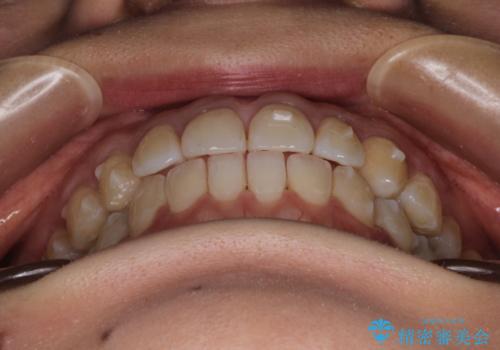

- 前歯の歯並びの改善を希望され来院された患者様です。

一度矯正治療をしたが、リテーナーをさぼってしまったため後戻りをしてしまった症例です。

初診時の歯並びの状態としては、上下ともに前歯部に限局した軽度ののがたつき(叢生)がある状態でした。

主に歯列弓の拡大とディスキング(歯と歯の間に隙間を作る処置)を行い叢生を改善しました。